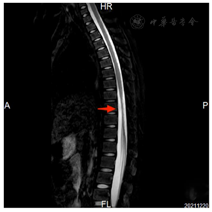

2021年7月16日胸椎MRI:胸7~9椎体水平以下脊髓信号异常,增强后示病灶强化不明显。2021年7月27日胸椎MRI增强(图1)提示胸9~10脊髓及脊髓圆锥内异常信号,出血?2021年8月10日MRI增强(图2)诊断为急性脊髓炎。2021年8月26日MRI增强(图3)提示急性脊髓炎伴脊神经炎,较前有所好转。2021年12月20日胸椎MRI增强(图4)提示急性脊髓炎伴脊神经炎,较2021年8月26日范围稍缩小。